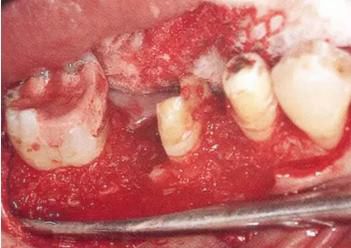

360截圖20170422102030273.jpg

▲圖11-3,4

▲圖11-3,4 齦瓣剝離翻開的狀態(tài)。右下6的遠(yuǎn)中牙根有較深的骨組織缺失,右下7的頰側(cè)有II度根分叉病變和近遠(yuǎn)中側(cè)有垂直型骨組織缺失。